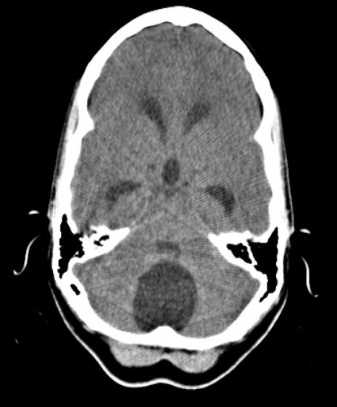

La evolución postquirúrgica fue favorable con regresión de las manifestaciones y sin complicaciones. En estudios de neuroimagen postquirúrgicos se constató la desaparición del quiste, la descompresión de las estructuras de fosa posterior y la restitución de la dinámica del LCR sin hidrocefalia. (Figura 5) Se logró su reintegración a la sociedad. En el seguimiento en consulta no se ha evidenciado recurrencia del quiste.

Fig.5. TAC simple de cráneo postoperatoria. Desaparición de la lesión. No hidrocefalia.